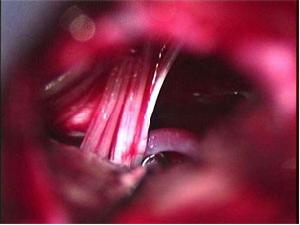

(2)神經手術:快刀切除痛性神經瘤,讓其固縮在血運豐富的軟組織內。神經瘤切除後,將神經分成兩束,兩束作端端吻接,有利於軸漿的循環流動平衡。切除疤痕較多和有張力的神經乾,代之以神經移植。